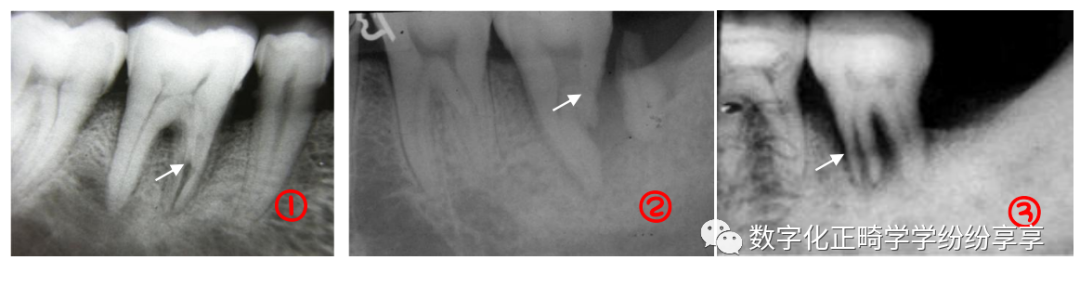

埋伏牙

曲面断层片怎么看正畸【曲面断层片(全景片)】如何解读和查看:牙周?牙体?牙髓?关节?_https://www.jmylbn.com_新闻资讯_第2张

牙髓疾病 dental pulp disease:

牙内吸收

患牙髓腔扩大,呈圆形/卵圆形/不规则形密度减低透射影。发生于根管者有长短不一、粗细不均、沿根管的扩大影。髓室壁或根管壁变薄。可伴有根尖吸收/感染/折断。

牙髓钙化

阻射影;后牙为圆形、卵圆形,可游离于髓室内,也可附着于髓室壁;前牙为条状或针状,充满于髓室或根管内,周围有线状低密度影像环绕。

正常髓室及根管影像完全消失,不能辨别出髓腔界线,有的尚可见,但很细。